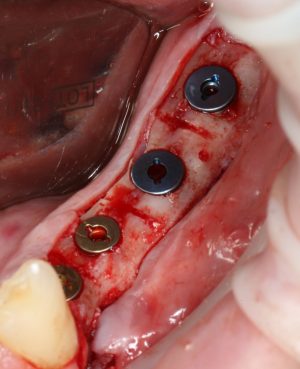

Использование металлоконструкций

И таки да, иногда можно обойтись без всякого металла. При условии, что перемещенный костный фрагмент нормально удерживается ригидностью слизистой оболочки или графтом:

Поэтому для реализации остеотомии нам нужны:

— винты. Разных размеров. Для фиксации пластин подойдут самые маленькие — 3-4 мм. Для фиксации самих костных фрагментов или «домкрата» потребуются винты длиннее — 10-12 мм.

— минипластины. Их выпускается огромное количество. Мы используем, в основном, X- и Н-образные минипластины наименьших размеров — с ними легче работать, они легко адаптируются, но есть и минус — иногда гнутся под нагрузкой.

При горизонтальной остеотомии, на мой взгляд, удобнее использовать минипластины. Как я уже отмечал выше, в практике мы используем X- и H-образные минипластины под винты размером 0.9х4мм. Количество металла в разных условиях может быть разным — всё зависит от того, на каком этапе достигается полная неподвижность перемещенного костного фрагмента.

В какой момент это делать? Наверное, если Вы используете графт в виде твердого блока, то, мне кажется. разумнее сначала уложить графт, затем проводить фиксацию перемещенного костного фрагмента винтами или минипластинами: